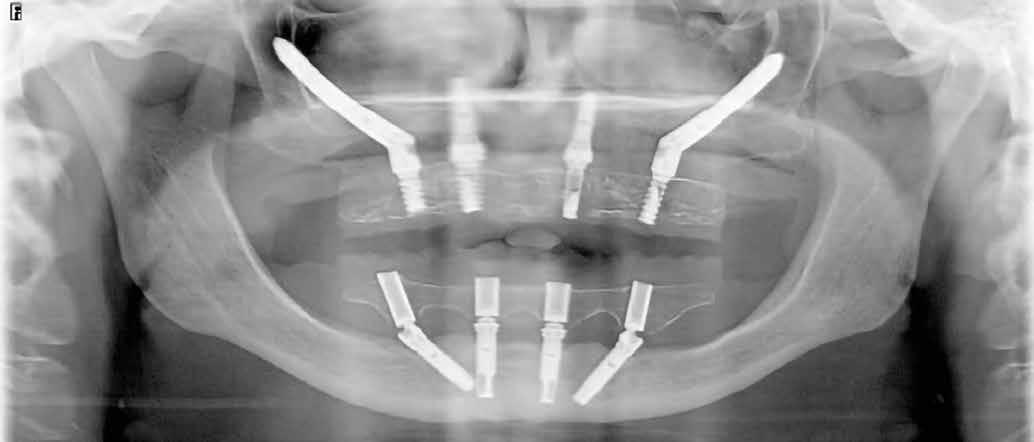

Mindkét kvadránsba behelyeztünk (>50 Ncm behajtási nyomatékkal) egy-egy 5 mm átmérőjű és 42,5 mm hosszúságú implantátumot (Nobel Zygoma 0°, Nobel Biocare), a második nagyőrlők helyére (4. ábra). Az implantátumok tengelyállásának kompenzálására 45°/6 mm magasságú tengelykorrekciós multi-unit fejeket használtunk (Multi-Unit Abutment, Nobel Biocare), amelyeket 30 Ncm nyomatékkal húztunk meg [17].

A frontrégióban (1.3 és 2.1) egy-egy 3,3 mm átmérőjű és 11,5 mm hosszúságú implantátumot (Nobel Speedy Groovy, Nobel Biocare) helyeztünk be, szintén >50 Ncm behajtási nyomatékkal, amelyekre 3 mm (1.3 helye) és 2 mm (2.1 helye) magas multi-unit fejek (Multi-Unit Abutment, Nobel Biocare) kerültek, 25 Ncm nyomatékkal meghúzva (5. ábra). A lebenyeket visszafektettük, majd a műtéti területet varrattal zártuk (4/0 selyem; B. Braun Medical; 6. ábra).

9. ábra: Posztoperatív panorámaröntgen.